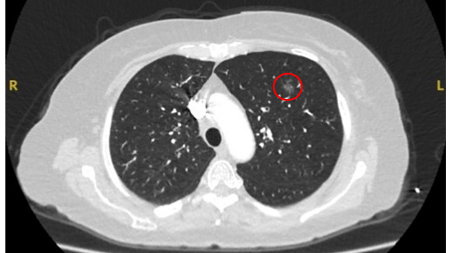

Tomografia computadorizada (TC) mostrando um pequeno nódulo no lobo superior esquerdo com margens lisas, posteriormente considerado uma metástase colorretal solitária na ressecção

Do acervo de Dr. George Tsaknis, MD, PhD, FRCP (Londres), MRQA, MAcadMEd, PGCert; usado com permissão